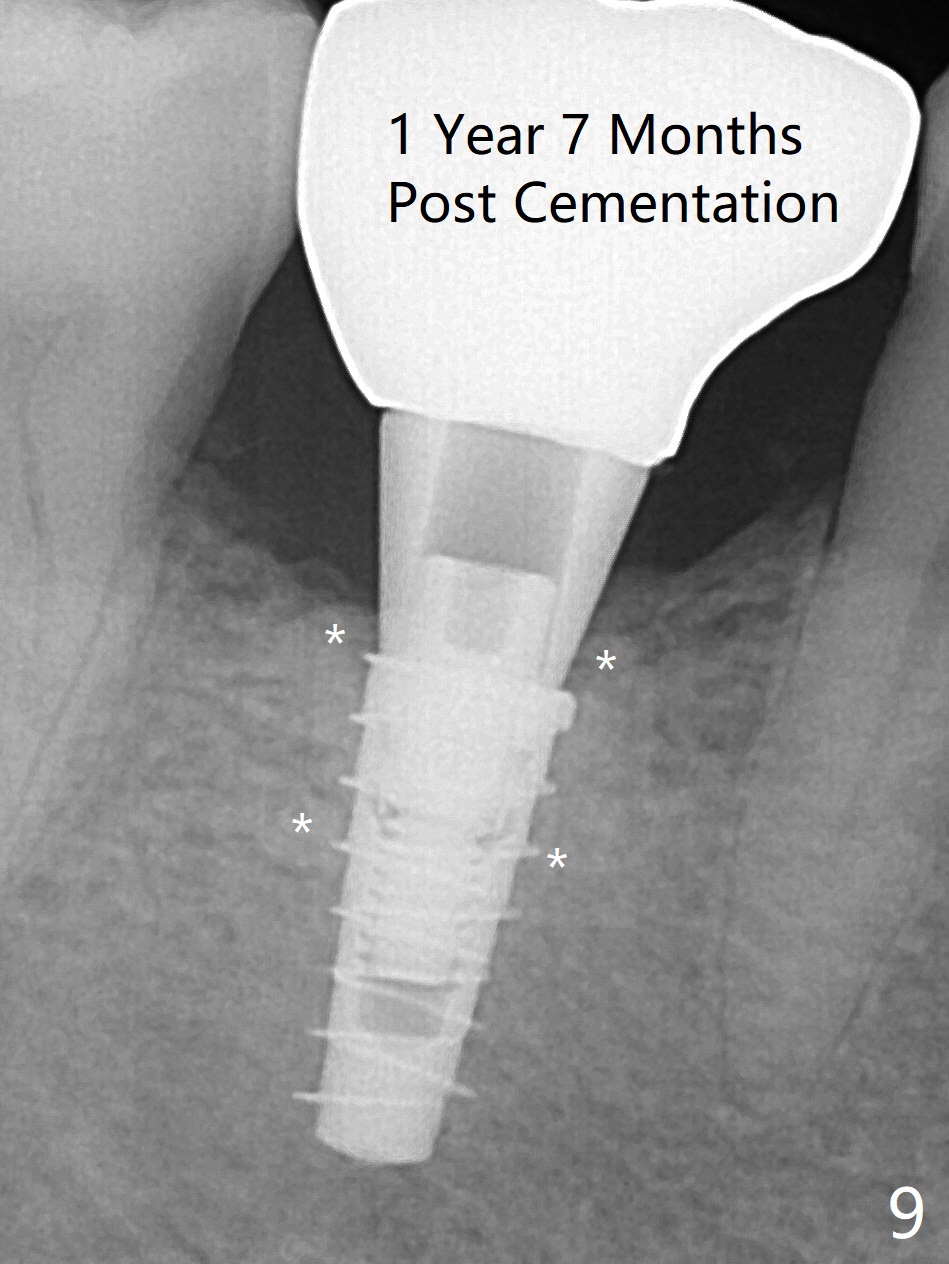

The retained deciduous tooth (lower right 2nd molar, Fig.1 T) has buccal apical infection and recession. After extraction, the initial depth of osteotomy is 11 mm over the flat socket bottom (Fig.2) without visible Mental Loop. Following 3.8 mm Magic Drill for 11 mm, a 4x11 mm dummy implant is placed partially due to hard bone; it appears that the apical osteotomy (Fig.3 yellow outline) overlaps the Mental Loop (red dashed line). For safety, a 4x9 mm IBS implant is placed with insertion torque 40 Ncm; a 5x5.7(4) mm abutment is immediately placed for an immediate provisional to cover the large socket and keep Vera graft in place (Fig.4 *). There is no postop paresthesia, probably due to the fact that the osteotomy is lingual to the Mental Loop. The provisional remains in place 7 days postop; its margin (Fig.5 arrow) covers the socket. The margin of the provisional is trimmed 1 month postop. Impression is taken nearly 3 months postop (Fig.6). The buccal plate looks atrophic 3 months postop (Fig.7 (immediately before cementation)), although there is no sign of periimplantitis. In the future, insert the immediate provisional inside of the buccal gingiva to make the buccal gingiva look bulky instead of buccal to it (Fig.5). The second drawback of placing an implant at the deciduous tooth area is that the crown is wide mesiodistally if orthodontic treatment is not rendered. Although there is lower anterior crowding, the patient declines orthodontic treatment. The bone density around the implant increases 7 months post cementation (Fig.8 *). The higher density bone seems to extend coronally 1 year 7 months post cementation (Fig.9). The dense bone apparently extends toward the abutment as well 3 years 5 months post cementation (Fig.10 curved arrows).